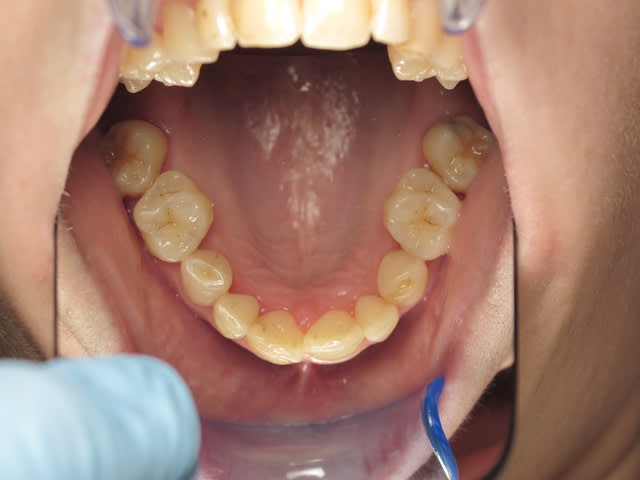

Patiente de 33 ans, questionnaire de santé RAS, demande esthétique. Elle souhaiterait que ses dents soient "davantage visibles" lors du sourire. Les dents absentes sont dues à des agénésies.

Il y a agénésies de 14-15 et 24-25, de 35 et 45 (restent 75 et 85), des molaires du bas. En haut j'avoue que je ne sais pas si ce sont des molaires de lait ou définitives...

Sa mère et sa soeur présentent les mêmes agénésies ou presque.

Perso, je proposerai de faire une solution de compromis plus light, avec génioplastie, rhinoplastie pour tricher et "décreuser" le profil, prévoir des implants en "7" en bas (et les pseudo-6 quand elles tomberont... plus tard), et revoir le secteur antérieur ( c'est quoi ces cacas composites sur 12, 11 et 21?)avec juste peut être un éclaircissement, pour un effet trompe-l'oeuil.

perso, ca me fait un peu alluciner la sévérité de vos propositions; d'après la seule photo, je ne dirais pas que la patiente ait un menton vraiiiiiiment en galoche, elle vient juste pour une petite (je maintiens) demande esthétique, pas pour un extreme makeover acec psychanalyse à la clef (qui a dit qu'elle nétait pas bien? elle a le droit que pas etre satisfaite de son sourire sans etre depressive!) et vous lui proposez chir ortho, odf, avec parfois génio plastie et rhinoplastie et vous dites que des petites facettes c'est irrémédiable.... c'est irrémédiable, mais bien faites, c'est les restaurations les plus sûres de la dentisterie... surtout que vue la palatoversion des incisives, y'aura pas trop à fraiser! Le diagnostic de rétroalvéolie (comment? moi je penche vers une liguoversion des insc, c'est tout) vous fait remettre en cause tout le tt odf d'un confrère qui, je pense aussi, n'a pas eu une situation idéale pour traiter...je pense qu'on a déjà pas mal eu d'interventions d'odf sur eugénol, quand on pensait à mettre des 8 à la place des 7, qui disaient que c'était loin d'etre aussi facile que ca, mais là, c'est encore plus difficile! Je pense que meme avec de la chir, le résultat ne sera pas génial, perso, je ne suis pas sûr que l'esthétique d'un maxillaire normopositionné avec des dents normoversées et des molaires à la place des premieres prémo soit top top, mais bon

Perso, ça me fait un peu halluciner que tu ne te rendes pas compte que des facettes vont juste lui prendre du pognon, pas lui redonner la visibilité de ses incisives, sauf à lui faire des ratiches de 2cm, et ce sera fragile et horrible. Ce qui lui manque (on a confirmé que le profil est concave) c'est une croissance antérieure et je pense vers le bas du maxillaire, elles sont très bien (quoiqu'un peu jaunes sur la photo), ses incisives!